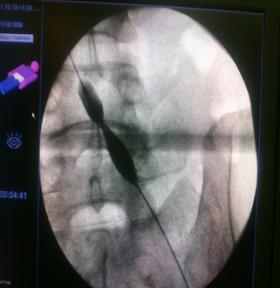

急诊造影:股总静脉、髂内外静脉大量新鲜血栓形成,见图4

图4